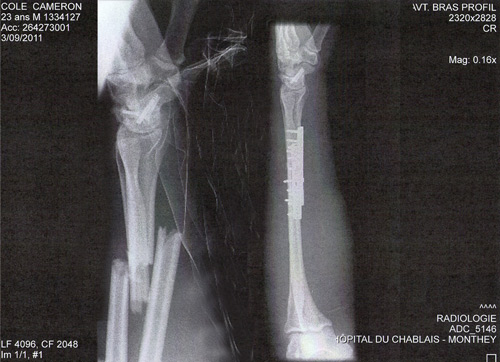

The decision to sit out the opening round of the 2012 UCI World Cup series was not any easy one for Kiwi downhill racer, Cameron Cole, who broke his wrist completely through during the Downhill World Championships last September.

It was at the 2011 World Championships held in September at Champery, Switzerland, that Cole broke his wrist after a fall in a practise run. Ironically, it was only 100m from where he’d fallen the previous year during a World Cup round, which resulted in a broken scaphoid.

Snapped: This X-Ray shows the broken arm of Team Lapierre International racer Cam Cole, of Christchurch, New Zealand, after a crash at the 2011 Downhill World Championships held in Champéry, Switzerland last September. Credit: Adventure Media Group/Cam Cole